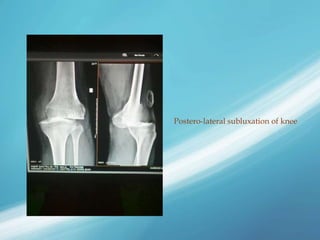

Postero-lateral subluxation of knee